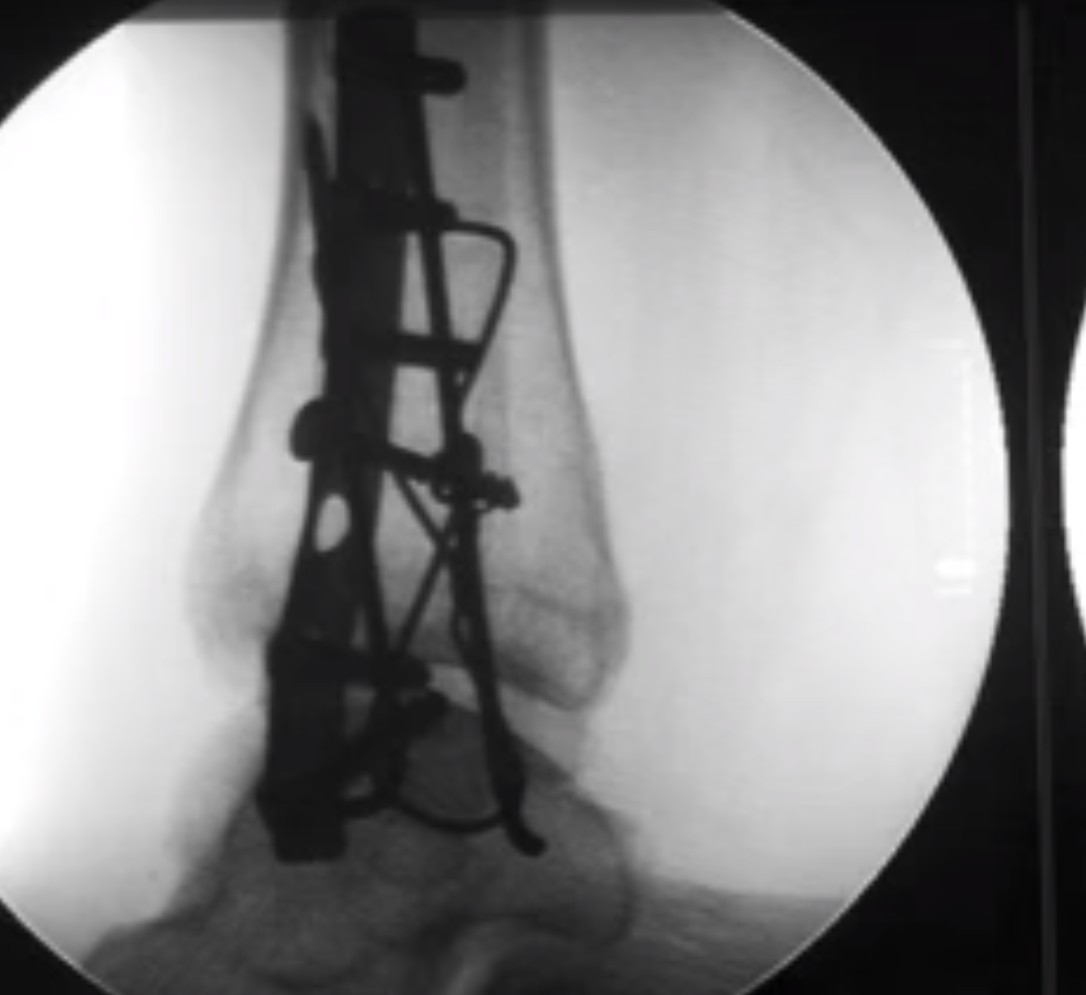

שבר באולקרנון

שבר באולקרנון, נפוץ כי מיקומו הבולט מהגוף הופך אותו לפגיע בטראומה ישירה. הוא אינו מכוסה או מוגן על ידי שרירים. כאשר השבר עם תזוזה, מנתחים לשם קיבוע פנימי (ORIF). עם מתכת, ברגים, וסיכות קירשנר. לא מקבעים בגבס, מכיוון ששריר הזרוע האחורי עוקר את העצם ממקומה.